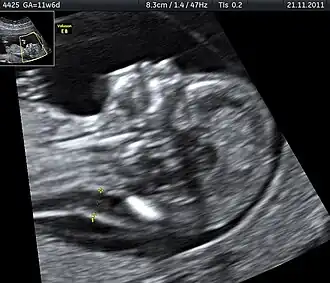

A ecografia permite diagnosticar muitos casos de morte fetal e de condições médicas que aumentam o risco

Método de diagnósticoFeto imóvel, ecografia[5]

Em muitos casos as causas são desconhecidas.[1] Entre as possíveis causas estão complicações da gravidez como pré-eclampsia e complicações do parto, problemas na placenta ou cordão umbilical, doenças congénitas, infeções como malária e sífilis, ou debilidade na saúde da mãe.[2][3][8] Entre os fatores de risco estão idade materna superior a 35 anos, tabagismo, consumo de drogas, reprodução medicamente assistida e primeira gravidez.[4] Suspeita-se de morte fetal quando não é sentido qualquer movimento do feto.[5] O diagnóstico pode ser confirmado com ecografia.[5]